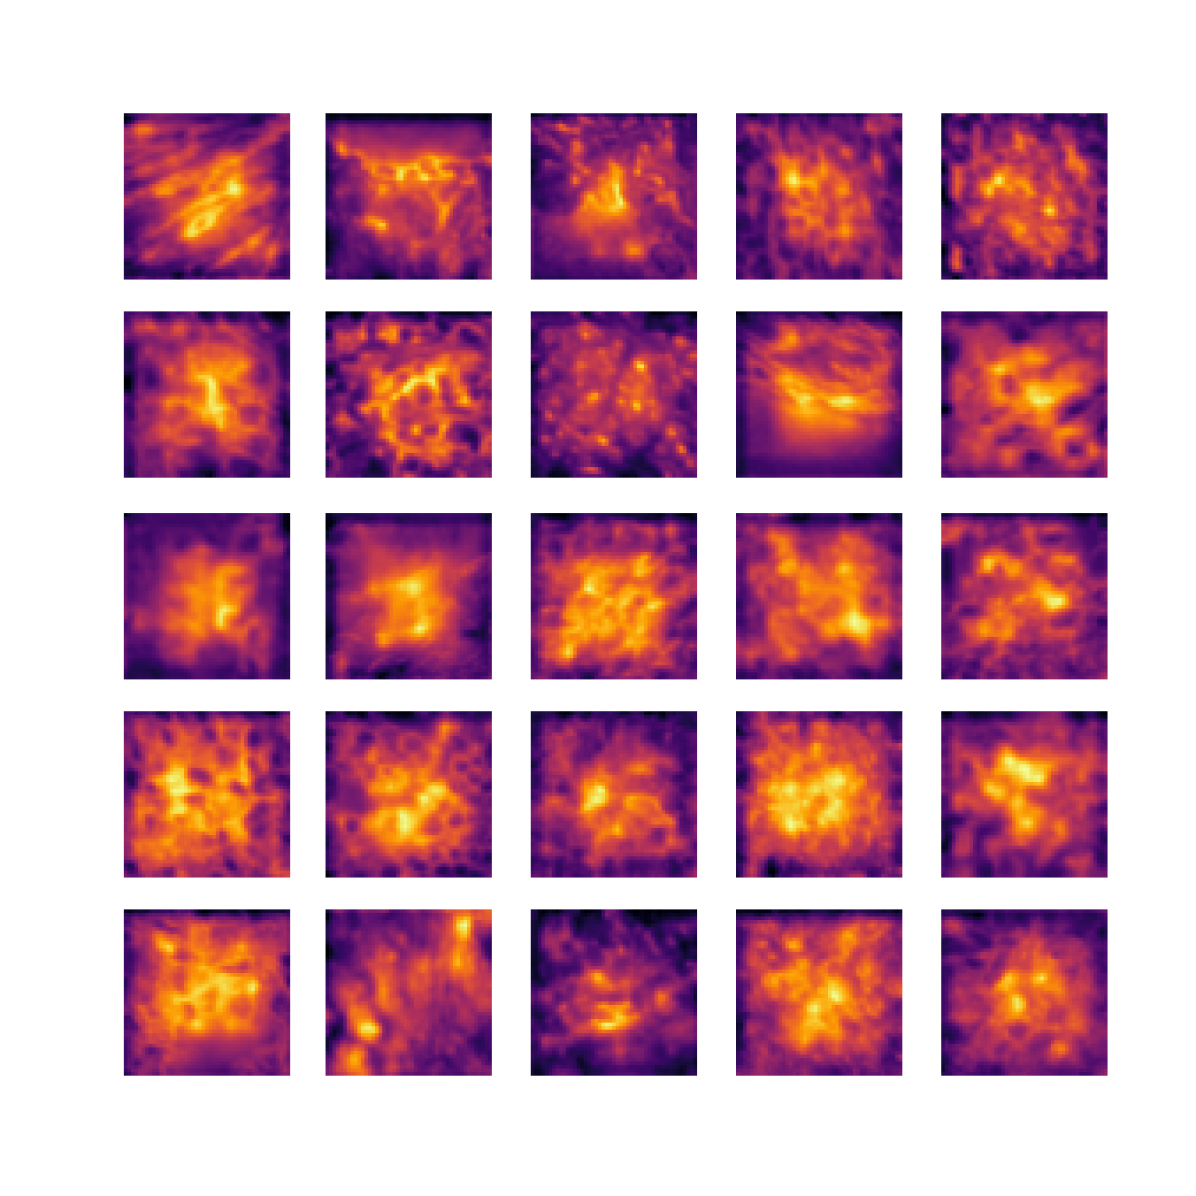

We also analyse the activation maps for each model using GradCAM as described in section S3. This offers more insight into the areas of the image which are contributing most heavily to the models’ representations. In Figure 4(b) we present some representative examples, however, a larger selection which was chosen at random is presented in Figures S10 to S25. The larger selection makes it easier to see the emergent patterns, including that privileged Siamese models tend to mainly identify features which are strongly present in both inputs, while unprivileged Siamese models tend to learn more diffuse features that are not specific to one cell phenotype or image region. TriDeNT ♆ incorporates both sets of features, learning both features specific to the privileged data and more the general features associated with unprivileged Siamese networks.

We can see in Figure 4(b) panel A that for ERG, the privileged Siamese model focuses almost exclusively on any nuclei which could be endothelial cells. As there are very few endothelial cells in the dataset, it could be an effective strategy to identify anything that could potentially be an endothelial cell to minimise the difference between the representations of the H&E model and the IF mask model. In the corresponding unprivileged Siamese image, we see that the model identifies some of these nuclei, albeit less strongly, but also focuses heavily on the other tissue and even the background, while strongly fixating on two spots of debris in the center of the image. This model has less ‘incentive’ to learn the weak features related to endothelial cells as these occur rarely and are not easy to detect, while more generic strong features such as the presence of connective tissue and the prevalence of background are more common and predictable from augmented images. We see that TriDeNT ♆ combines these two feature sets, strongly identifying nuclei while also identifying the connective tissue.

In panel C we see a similar pattern, with the privileged Siamese model fixating solely on the nuclei, while the TriDeNT ♆ model takes a more balanced approach. The unprivileged Siamese model appears to focus on a single cluster of nuclei while neglecting others, and similarly identifies an area of fibroblasts with its distinctive pattern but does not others.

In contrast to panels A and C which represent models with poor privileged Siamese results, panels B and D represent models whose privileged Siamese results were comparable to both TriDeNT ♆ and even the supervised baseline. It is therefore interesting to note that there are far more similarities between the privileged Siamese and TriDeNT ♆ models in both cases. Particularly in panel B, TriDeNT ♆ and the privileged Siamese model return virtually identical heatmaps, with both strongly identifying epithelial nuclei and neglecting the same areas of connective tissue. The unprivileged model in this case appears to focus solely on the centre of the image, giving a significantly different heatmap to the other panels.

Panel D again shows the previous pattern, with the privileged Siamese model identifying the features strongly present in the privileged data – fibroblasts – while neglecting the nuclei present. TriDeNT ♆ also strongly identifies the connective tissue, but, unlike the privileged Siamese model, does not completely neglect the nuclei. The unprivileged Siamese model primarily identifies background, and does not appear to identify the nuclei in this example.